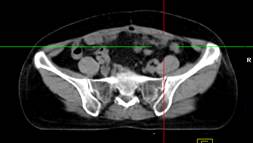

Hình 1. Bệnh nhân Nguyễn Th. H., nữ, 43 tuổi, chẩn đoán ung thư buồng trứng phải. Trên hình FDG-PET/CT thấy khối u buồng trứng phải tăng hấp thu FDG.